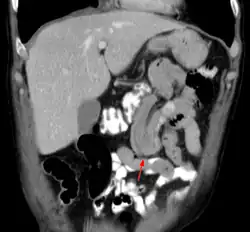

Die diagnostische Standardmethode ist eine Computertomographie des Bauches[8] und die Sonografie.[7] Nicht selten wird die Diagnose auch erst gestellt, wenn zur Diagnosefindung der Bauchraum chirurgisch geöffnet wird (eine so genannte Probelaparatomie).